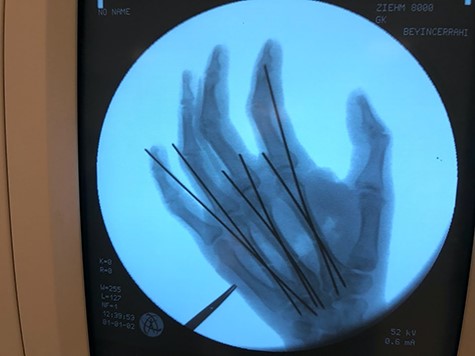

A 27-year-old male was admitted to the emergency room after blunt trauma on the dorsum of the right hand. In his physical examination, circulation and sensory findings were normal, but the motor functions were limited. On the X-ray radiograph, metacarpal base fractures were detected in the index, middle and ring fingers (Figs 1 and 2). After the surgical area was sterilized, the dissection was initiated under tourniquet and general anesthesia. Tendons were found to be intact due to blunt trauma, and the metacarpal base fractures in fingers were exposed (Fig. 3). These bones were stabilized with Kirschner wires (Fig. 4). After the debridement of dead tissues and opening the tourniquet, bleeding was controlled, and skin was stapled. The flap was planned for the 2 x 2 cm defect, which corresponds to the third metacarpal bone and exposed the tendon and bone (Fig. 5). The first dorsal metacarpal artery (FDMA) flap was initially considered; however, a dorsoradial artery flap was preferred since the dissection reached to the second metacarpal bone.

Exposing the metacarpal fractures. In the second (C), third (B) and fourth (A) fingers and intact tendons. Flap marking intraoperatively: yellow arrow.